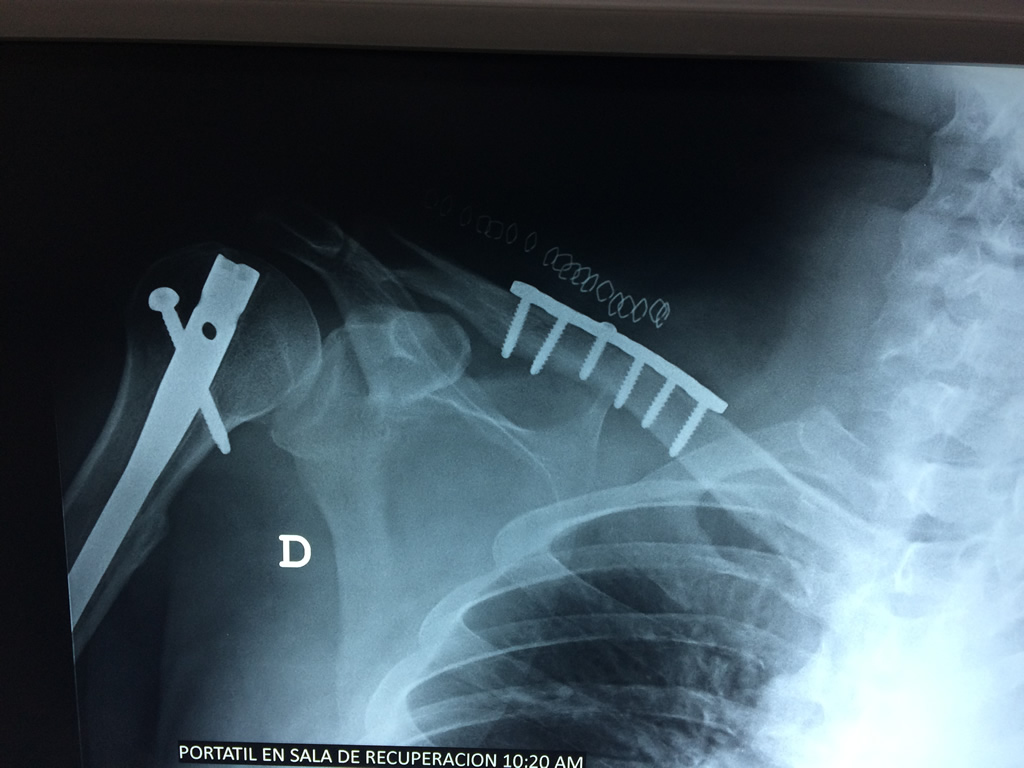

Cirugias en El Salvador - Clavícula

La clavícula es un hueso largo, con forma de "S" itálica, situado en la parte anterosuperior del tórax. Junto con la escápula forman la cintura escapular. Se puede palpar por toda su longitud y se extiende del esternón al acromion de la escápula, siguiendo una dirección oblicua lateral y posterior.